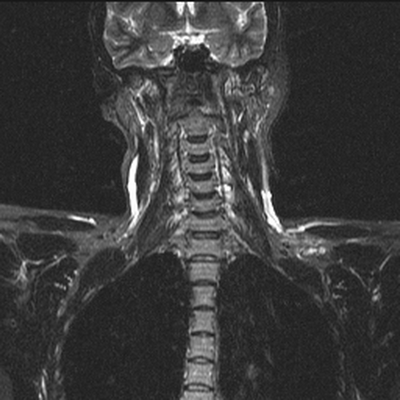

На сериях МРТ, выполненных в аксиальной, корональной и сагиттальной плоскостях, взвешенных по Т2-ВИ, Т1-ВИ и STIR-ИП, получены изображения шейного отдела позвоночника.

Определяется патологический кифоз с вершиной на уровне тел позвонков С5-С6.

Выявляются дегенеративно-дистрофические изменения в виде умеренно выраженного понижения интенсивности сигнала от межпозвонковых дисков в сегментах С2-Th1, со снижением высоты в сегментах С5-С7, а также формирования передних и заднебоковых краевых костных разрастаний. Унковертебральный артроз на уровне сегментов С5-С7.

В смежных отделах позвонков С6-С7 определяются зоны гиперинтенсивного МР-сигнала на Т2-ВИ, STIR-ИП и гипоинтенсивного в Т1-ВИ (вероятно, обусловленные отёком вещества костного мозга).

Определяются неровности смежных замыкательных пластин тел позвонков С5-С7 за счет хрящевых узлов Шморля.

В сегменте С3-С4 под краевыми остеофитами определяется дорзальная медианная протрузия межпозвонкового диска, размером до 2,5мм. Переднее субарахноидальное пространство деформировано. Межпозвонковые отверстия умеренно сужены, достоверных данных за компрессию корешков нервов не выявлено. Передне-задний размер позвоночного канала до 14мм.

В сегменте С5-С6 под краевыми остеофитами определяется задняя диффузная протрузия межпозвонкового диска, размером до 2,5мм. Переднее субарахноидальное пространство деформировано. Межпозвонковые отверстия умеренно сужены, достоверных данных за компрессию корешков нервов не выявлено. Передне-задний размер позвоночного канала до 13мм.

В сегменте С6-С7 под краевыми остеофитами определяется задняя диффузная протрузия межпозвонкового диска, размером до 2мм. Переднее субарахноидальное пространство деформировано. Межпозвонковые отверстия умеренно сужены, достоверных данных за компрессию корешков нервов не выявлено. Передне-задний размер позвоночного канала до 14мм.

Сигнальные характеристики от шейных позвонков не изменены.

Видимые отделы спинного мозга в размерах не увеличены, имеют четкие контуры и однородную структуру, интенсивность МР сигнала не изменена.

Паравертебральные мягкие ткани не изменены.

МР-признаки дегенеративно-дистрофических изменений шейного отдела позвоночника с нарушением статики. Протрузии дисков на уровне сегментов С3-С4, С5-С6, С6-С7. Унковертебральный артроз. Хрящевые узлы Шморля смежных замыкательных пластин тел позвонков С5-С7.